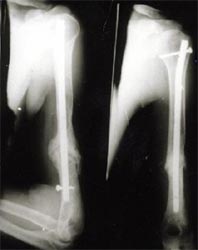

病例一、患者男性,60岁,肱骨远段开放粉碎骨折3年,骨不连,假关节形成。

图1-1我们用钢板固定骨折端提供支撑力,患者自体骨髓细胞经与异体骨和骨生长因子复合,

使没有细胞的植骨材料变成了有细胞的活骨。

图1-2 骨折在12个月后愈合,功能恢复满意。